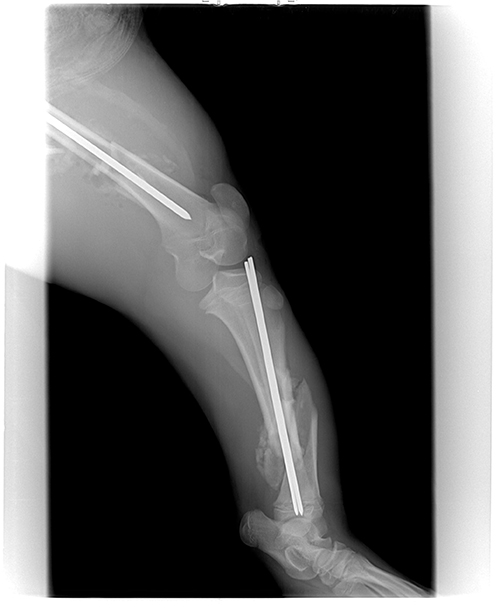

By day 14 our veterinarian felt he was strong enough to set his leg. Both large bones in his left hind leg were badly broken (see pictures above). The operation took almost five hours. She put rods through the center of the bones. It was a very big job, but everything went well.

On Jan. 1, 2013, Frank’s veterinarian X-rayed his leg again to see if it had healed properly and to see if the rods needed to be removed. She was very happy with how the leg had healed. She needed to remove only one of the rods. Frank now had only 30 days more to heal from having the rod removed and then he would be able to move in with the girls.